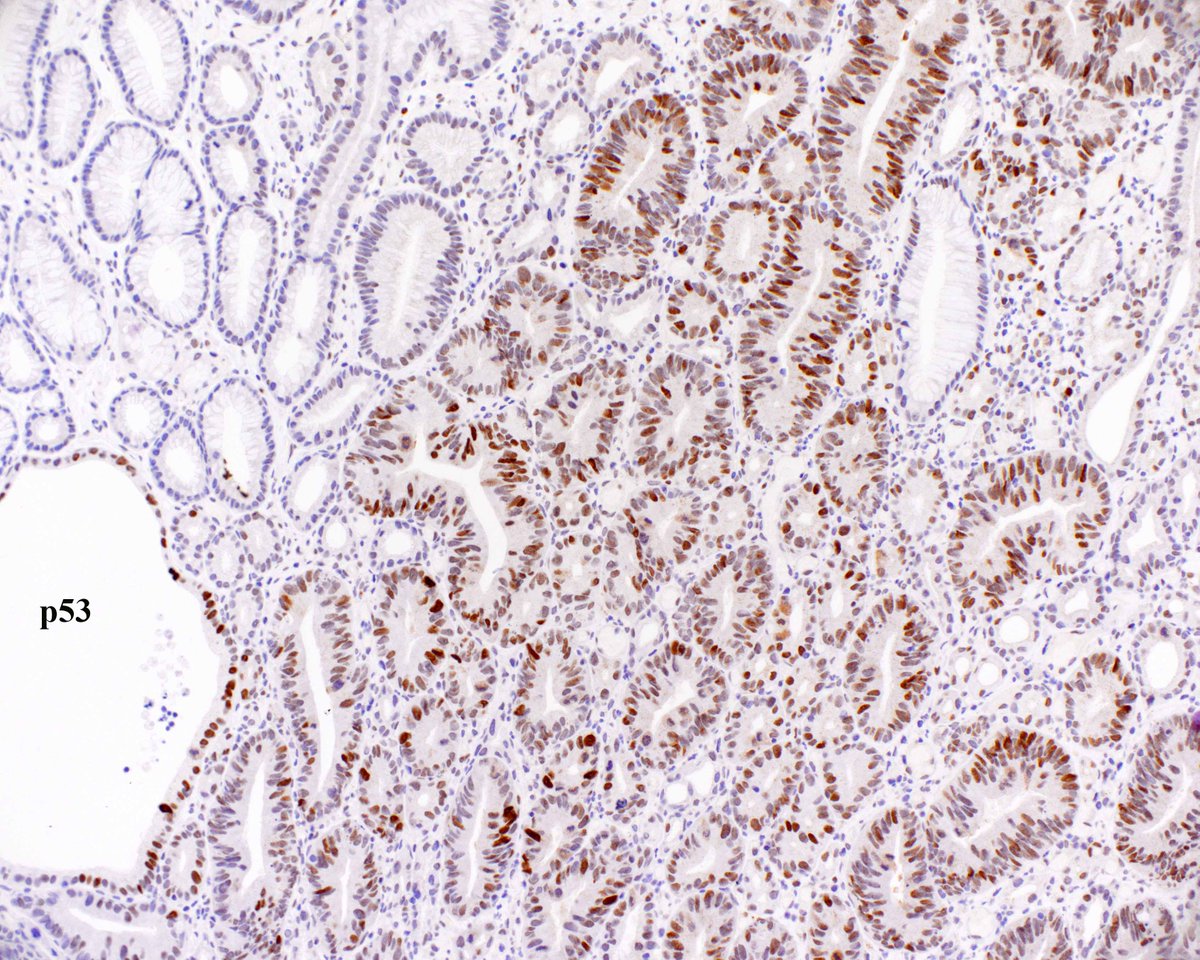

34 year old female abdomen, sent in as cyst #dermpath David Terrano Mariantonieta Tirado Allison Osmond MD MSc FRCPC Dermpath_doc_trish Henry YANG Olaleke Folaranmi Pathology Jerad Gardner, MD Christine J. Ko, MD Lorand Kis James Sampson American Society of Dermatopathology #BSTPath